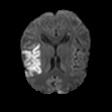

We conducted experiments on four brain imaging datasets: BraTS2017, BraTS2018, BraTS2019, and ISLES2022 [33, 34, 35, 36]. The BraTS datasets, developed for the MICCAI brain tumor segmentation challenge, contain 285, 285, and 335 labeled cases respectively, categorized into high-grade and low-grade gliomas. Each case includes 3D MRI scans from four modalities (T1, T2, FLAIR, T1c); we primarily used FLAIR. Preprocessing involved brain region cropping and intensity normalization. Dataset splits were 200/25/60 as train/val/test for BraTS2017 and BraTS2018, and 250/25/60 for BraTS2019. All experiments were conducted independently with models trained from scratch.

ISLES2022 focuses on stroke lesion segmentation in 3D multimodal MRI, with 250 cases including DWI, ADC, and FLAIR. We used DWI and split the dataset into 150 training, 40 validation, and 60 testing samples.

Quantitative Results. Tables 3–4 report results on BraTS2019, BraTS-2018, BraTS2017, and ISLES2022 datasets with limited labeled data (4% or 10%). On BraTS2019, our method outperformed most competitors in Dice, Jaccard, and 95HD, with a notable lead under the 4% setting, despite slightly lower ASD. On BraTS2018, it consistently surpassed all baselines, achieving nearly 2% higher Dice than the runner-up. It also achieved top performance on all metrics for BraTS2017, highlighting strong robustness and generalization. For ISLES2022 with 10% labeled data, our method significantly outperformed DAE-MT and closely matched the fully supervised model.

Qualitative Results. Figures 4, 3 present visual comparisons of the predicted segmentation results from our method and other baselines on the middle slice of the BraTS2018, BraTS2019, and ISLES2022 datasets. Our method demonstrates greater robustness and better coverage of the ground truth regions, particularly in areas where other methods fail to identify lesions and incorrectly classify them as background. Furthermore, our approach yields more accurate boundaries and preserves the overall shape of the target structures more effectively than competing methods.